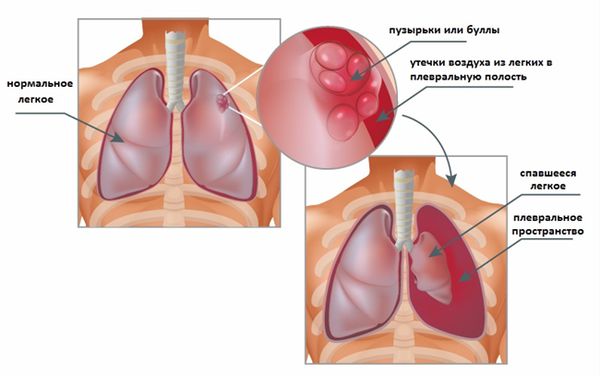

Диагностика плеврального выпота: что нужно знать